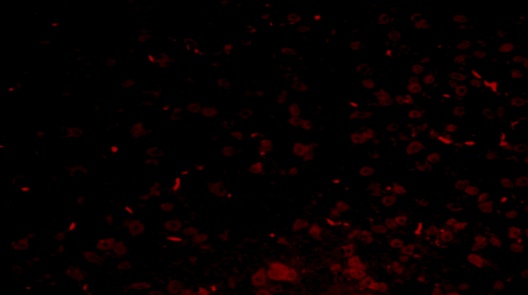

TEL increased NeuN expressions in MPTP intoxicated mice brain

SNpc and ST regions of MPTP mice brain showed a significant decrease in % NeuN immunopositive cells [F (4,10) = 274.1, p<0.01 and F (4,10) = 86.24, p<0.01, respectively] when compared to the vehicle treated mice. TEL (3 and 10 mg/kg) significantly (p<0.01) increased % NeuN immunopositive cells in both the regions in comparison to MPTP mice (fig. 4).

Fig. 4: Effect of TEL on % NeuN immunopositive cells in MPTP intoxicated mice brain. Pictures represent NeuN immunopositive cells of (A) SNPc and (B) ST brain regions X 400 magnification. (1) Normal control, (2) MPTP induced mice brain, (3) TEL (3 mg/kg b. wt.) administered MPTP mice brain, (4) TEL (10 mg/kg b. wt.) administered MPTP mice brain and (5) TEL (10 mg/kg b. wt.) administered normal mice brain. (C) Values were expressed in mean±SEM, n=4 animals/group, statistical analysis was performed using one way ANOVA followed by Tukey’s multiple comparison test, ## indicates p value<0.01 Vs group I, ** indicates p value<0.01 Vs group II